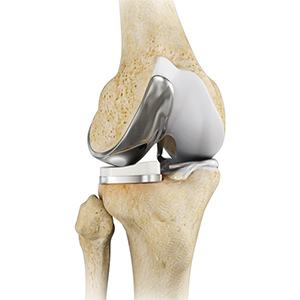

Total Knee Replacement

Total knee replacement, also called total knee arthroplasty, is a surgical procedure in which the worn out or damaged surfaces of the knee joint are removed and replaced with an artificial prosthesis. The knee is made up of the femur (thighbone), tibia (shinbone) and patella (kneecap). The two menisci, the soft cartilage between the femur and tibia